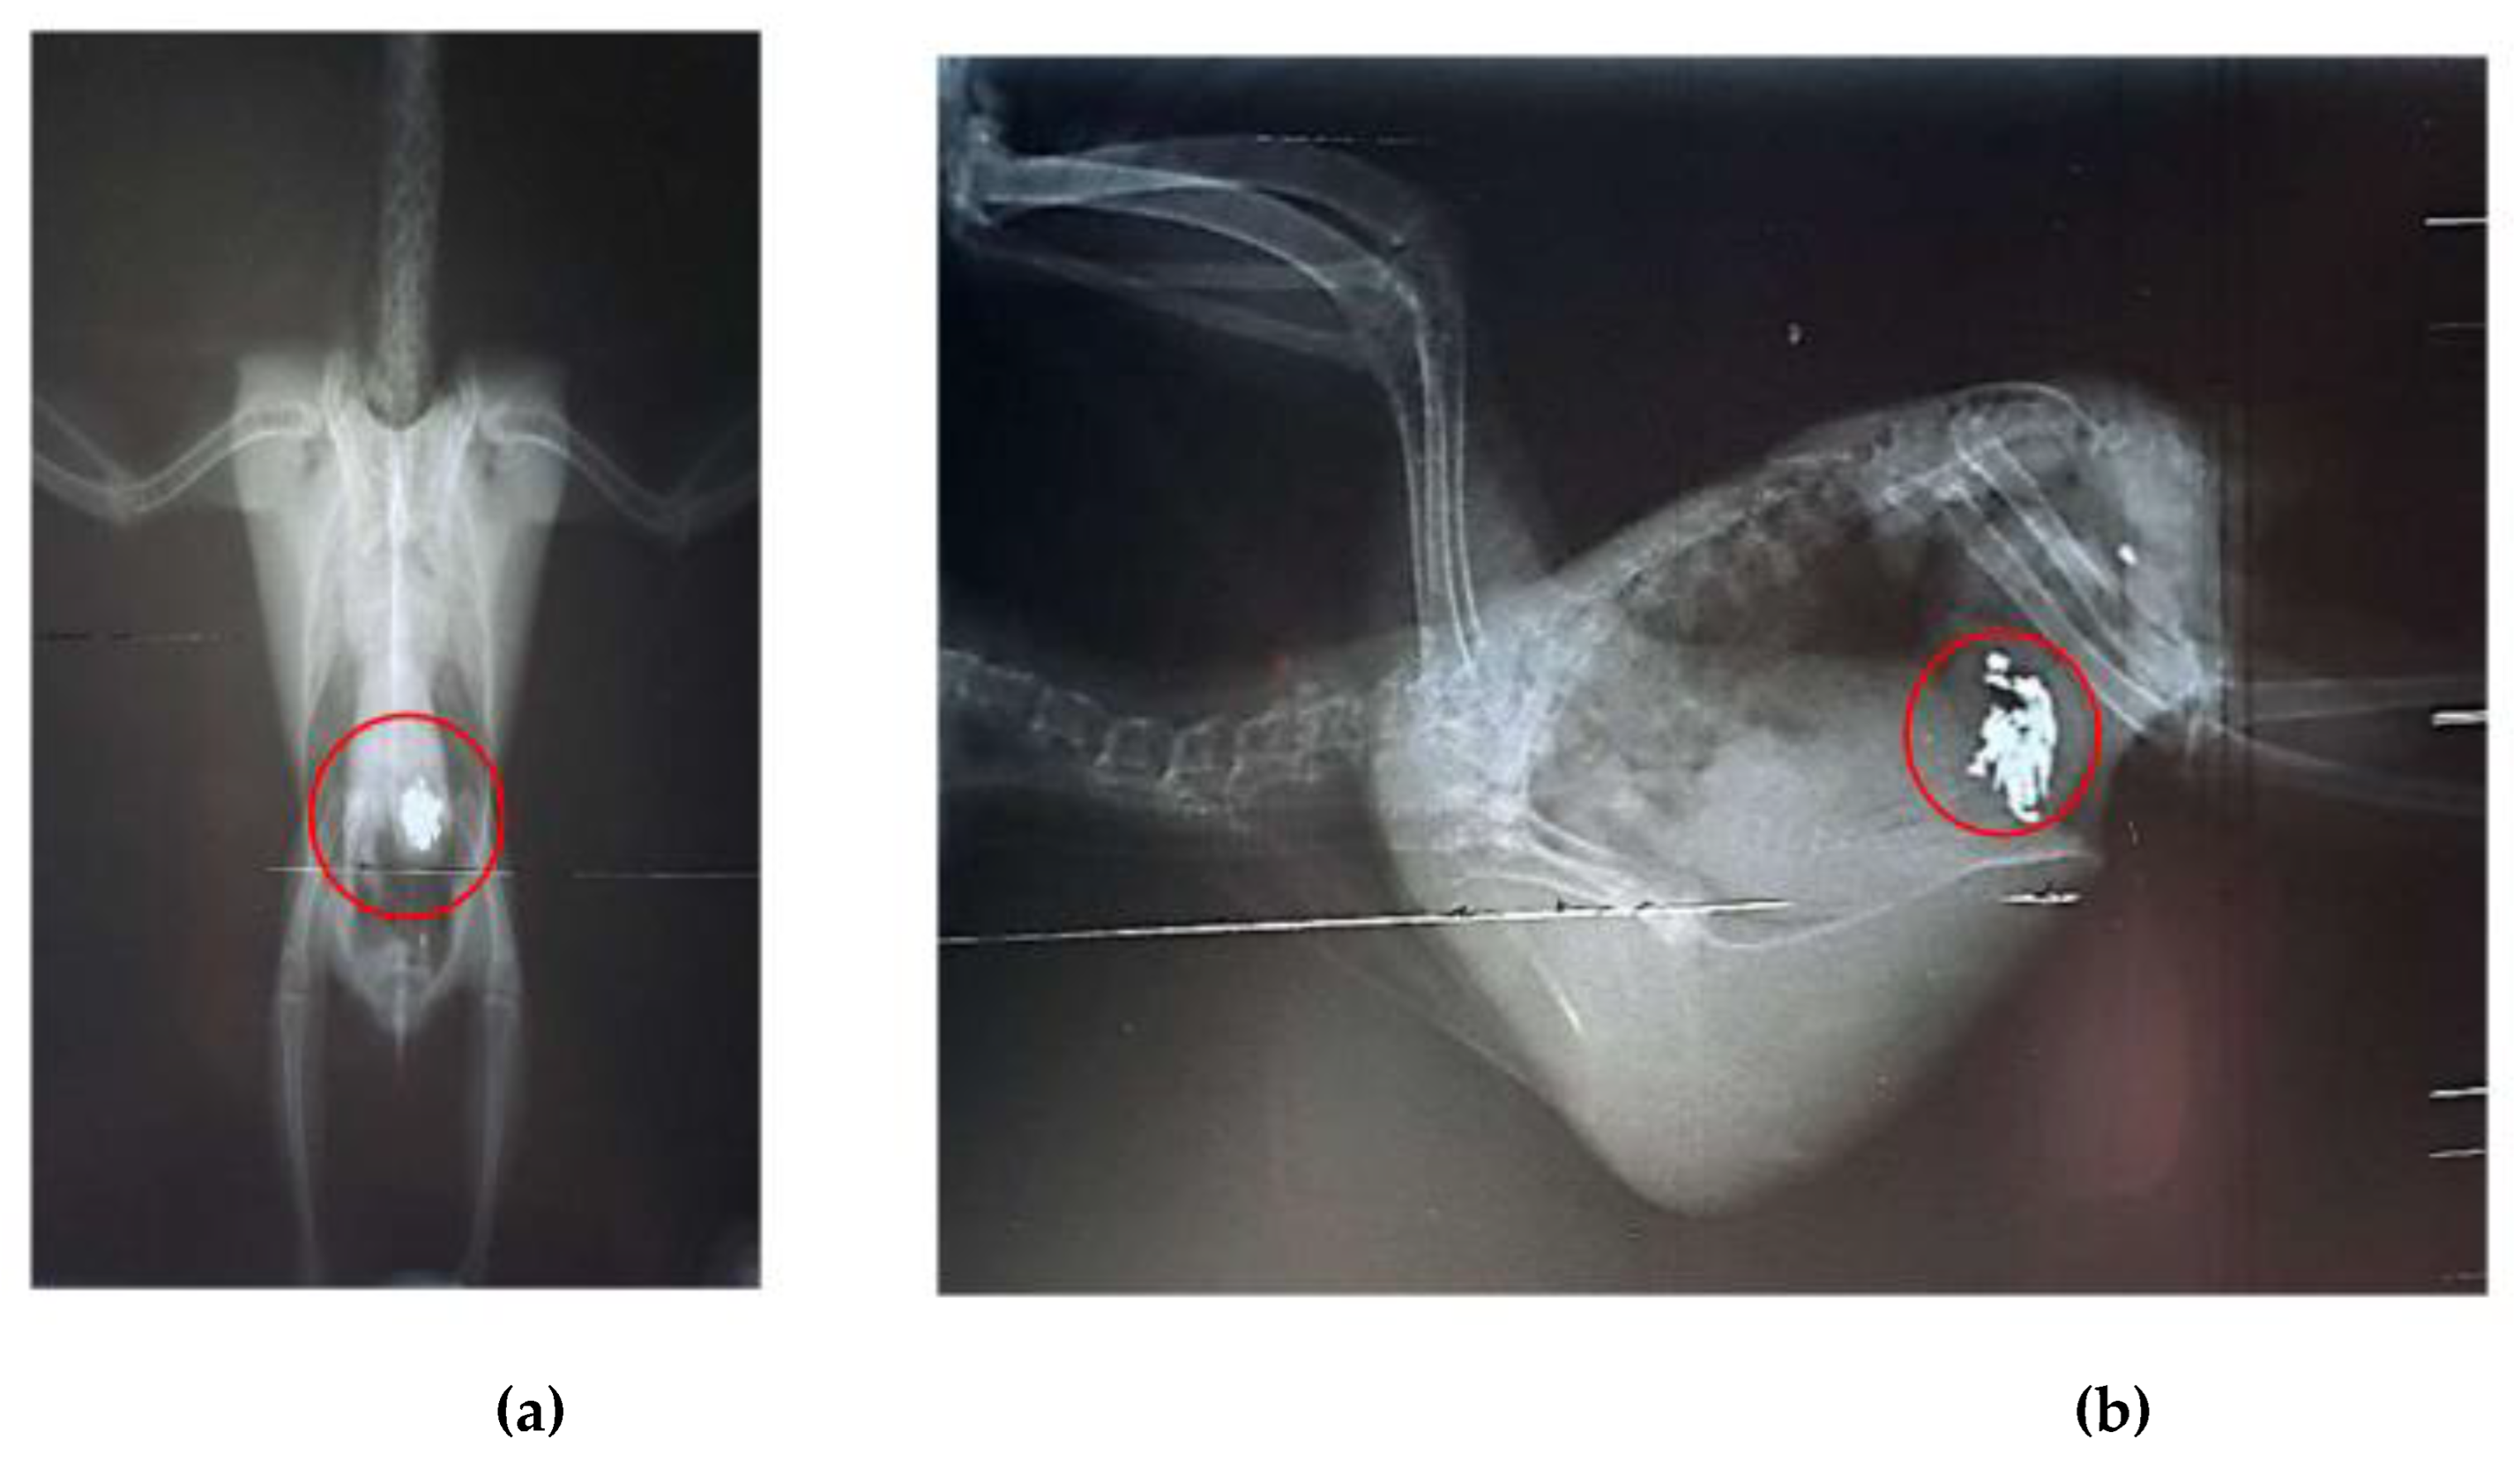

After seven days of chelation therapy, the birds underwent repeat radiographs of the coelomic cavity under sedation with intranasal midazolam (0.01 ml). In these radiographs, a reduction in the amount of metallic content in the ventriculus of bird 1 was observed, and chelation therapy with calcium EDTA was continued for an additional three days. For bird 2, the radiographs taken after the start of chelation therapy showed no remaining foreign bodies in the ventriculus; however, an area of radiopacity was noted in the pulmonary field (Figures 5A, B). It is important to note that no metallic objects were observed in the feces of either bird.

Figure 5. Radiographic examination of the coelomic cavity in two specimens of Aratinga jandaya. (a) Ventrodorsal projection – quantitative reduction of radiopaque content compared to the first examination (marked in red) in the ventricular region the bird 1. (b) Ventrodorsal projection – presence of a few radiopaque foreign bodies (marked in red) in the second bird.